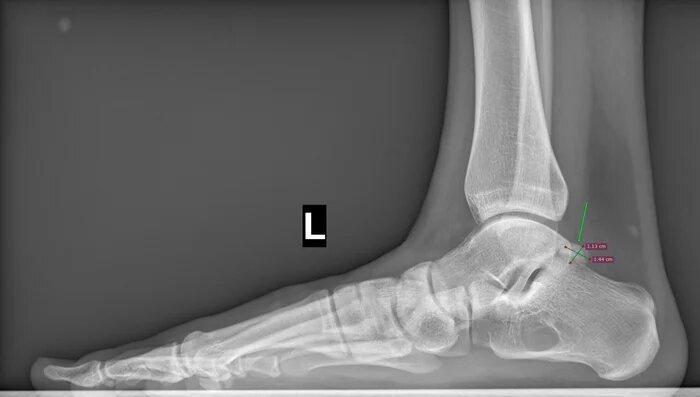

На Р-грамме левой стопы с нагрузкой: в структуре пяточной кости отмечается зона просветления костной ткани размером 29х27х17мм (точные размеры по данным КТ, которая была пройдена призывником),неправильной овоидной формы, с склеротическим контуром, соответствует кисте левой пяточной кости.

По заднему контуру таранной кости визуализируется добавочная кость- os trigonum размером 1.1х1.5см,наиболее вероятно вызывающая импиджмент-синдром заднего отдела голеностопного сустава.

Угол продольного свода левой стопы 160 град., высота 19 мм, соответствует продольному плоскостопию 3 ст. левой стопы.